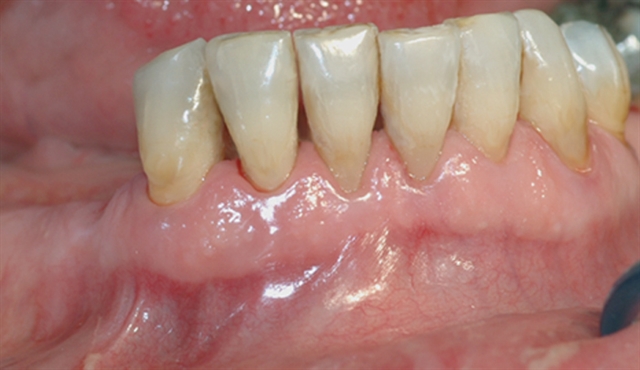

perio stor 2

En undersøkelse med lommeregistrering avdekker likevel et omfattende bentap ved den ene tannen.